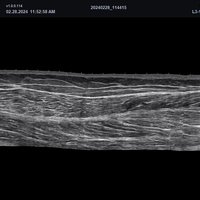

• L3-15H (3-15 MHz) für Ultraschalluntersuchungen in den Bereichen Gefäße, Weichteile, Bewegungsapparat (MSK)

• L3-12H WD (3-12 MHz) für Ultraschalluntersuchungen in den Bereichen Gefäße, Weichteile, Bewegungsapparat (MSK), Pädiatrie

• L3-8H (3-8 MHz) für Ultraschalluntersuchungen in den Bereichen Gefäße, Bewegungsapparat (MSK), Pädiatrie